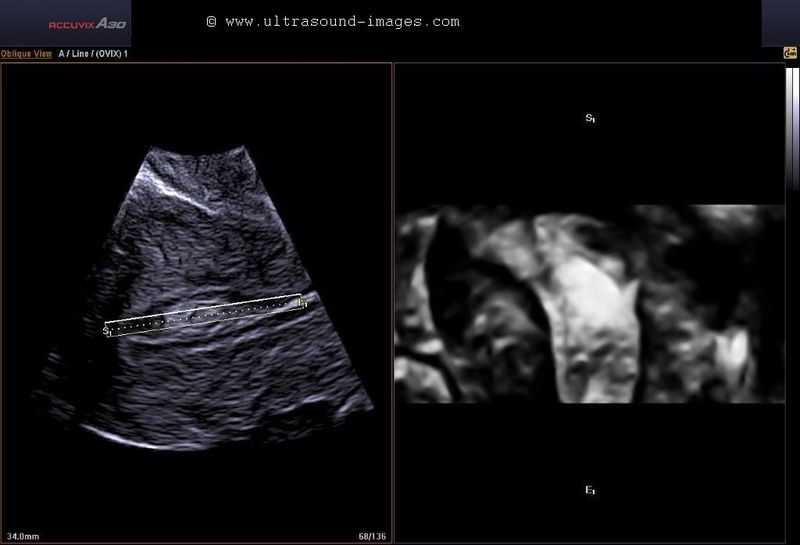

case-2: Submucous fibroid: (3-D imaging)

Here are some interesting ultrasound images if a submucous fibroid using a new technique called Volume contrast imaging. This renders 2 D image sections of a volume image (3-D image) acquired of the part being studied (here the Uterus). (Images courtesy of Dr. PK Srivastava, India).

This technique appears to be an application of 3D/ 4D ultrasound. Observe how volume contrast ultrasound images of the uterus bring out the fine detail of the submucous fibroid and its margins. The image on lower right shows the 3-D ultrasound appearance of the disease